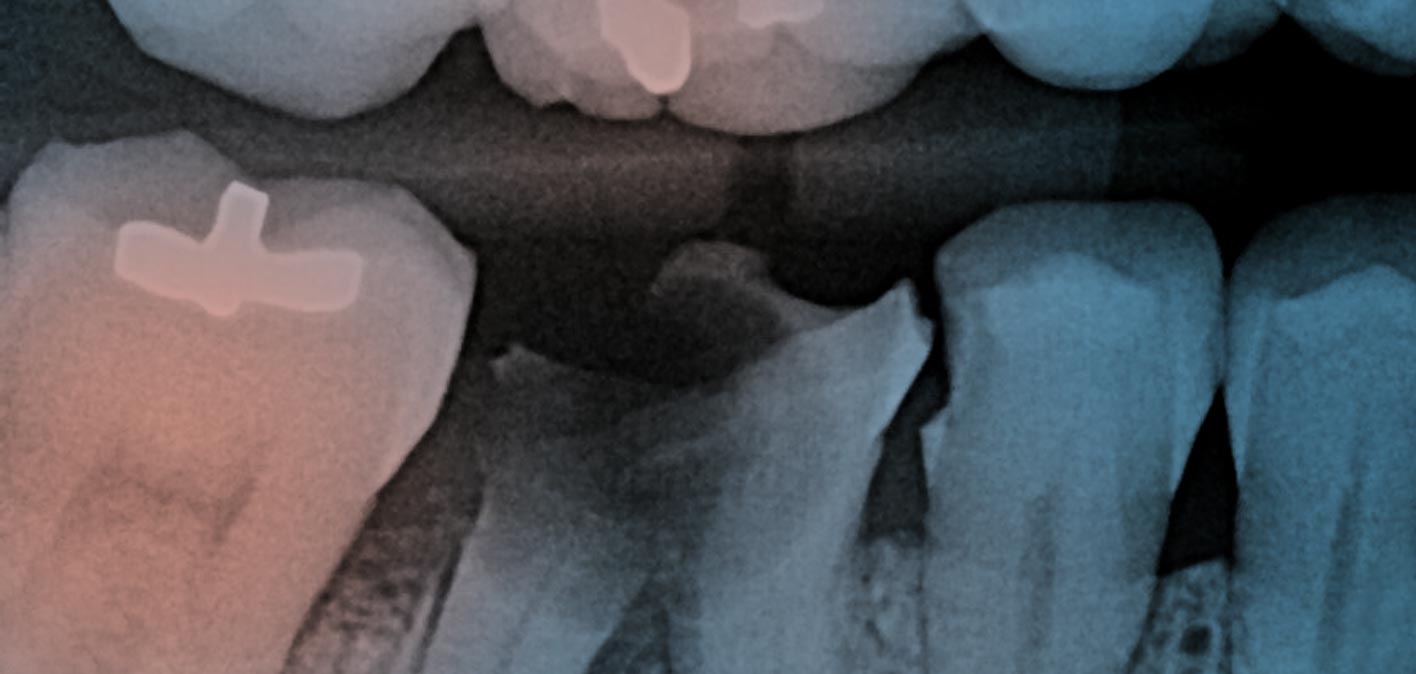

The wisdom teeth are the final set of adult molars. They should emerge behind the second row of molars, but in many cases there isn’t enough room in the jaw for them to grow properly. In these cases, the wisdom teeth can cause damage to your other teeth and your gums. We assess wisdom teeth on a case-by-case basis to determine if they need to be removed. Depending on your individual case we may be able to extract the teeth in our office or we may refer you to an oral surgeon.